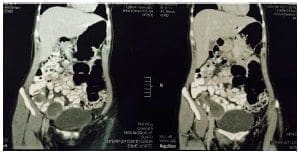

En la ecografía transvaginal se observó una masa abdomino-pélvica quística y compleja, de origen indeterminado, y en la tomografía computadorizada (TC) abdomino-pélvica con contraste, una imagen sugestiva de mucocele apendicular o masa anexial compleja derecha y miomatosis uterina múltiple, sin evidencia de adenopatía pélvica o a distancia (figuras 1 y 2). Además, la colonoscopia reportó una masa apendicular grande y subepitelial.

Tomografía computadorizada abdomino-pélvica con contrasteFigura 2. Tomografía computadorizada abdomino-pélvica con contraste: imagen sugestiva de mucocele apendicular o masa anexial compleja derecha